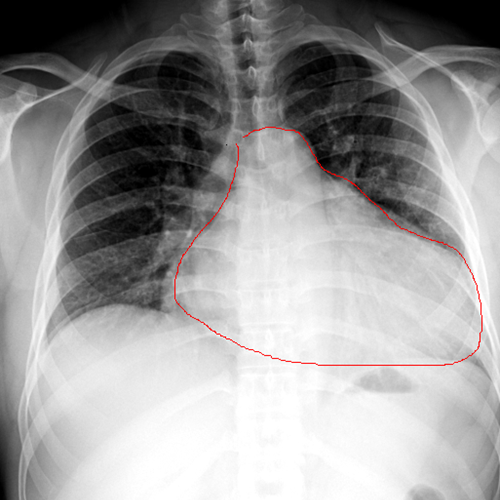

胸片提示:心影增大(左心为主)